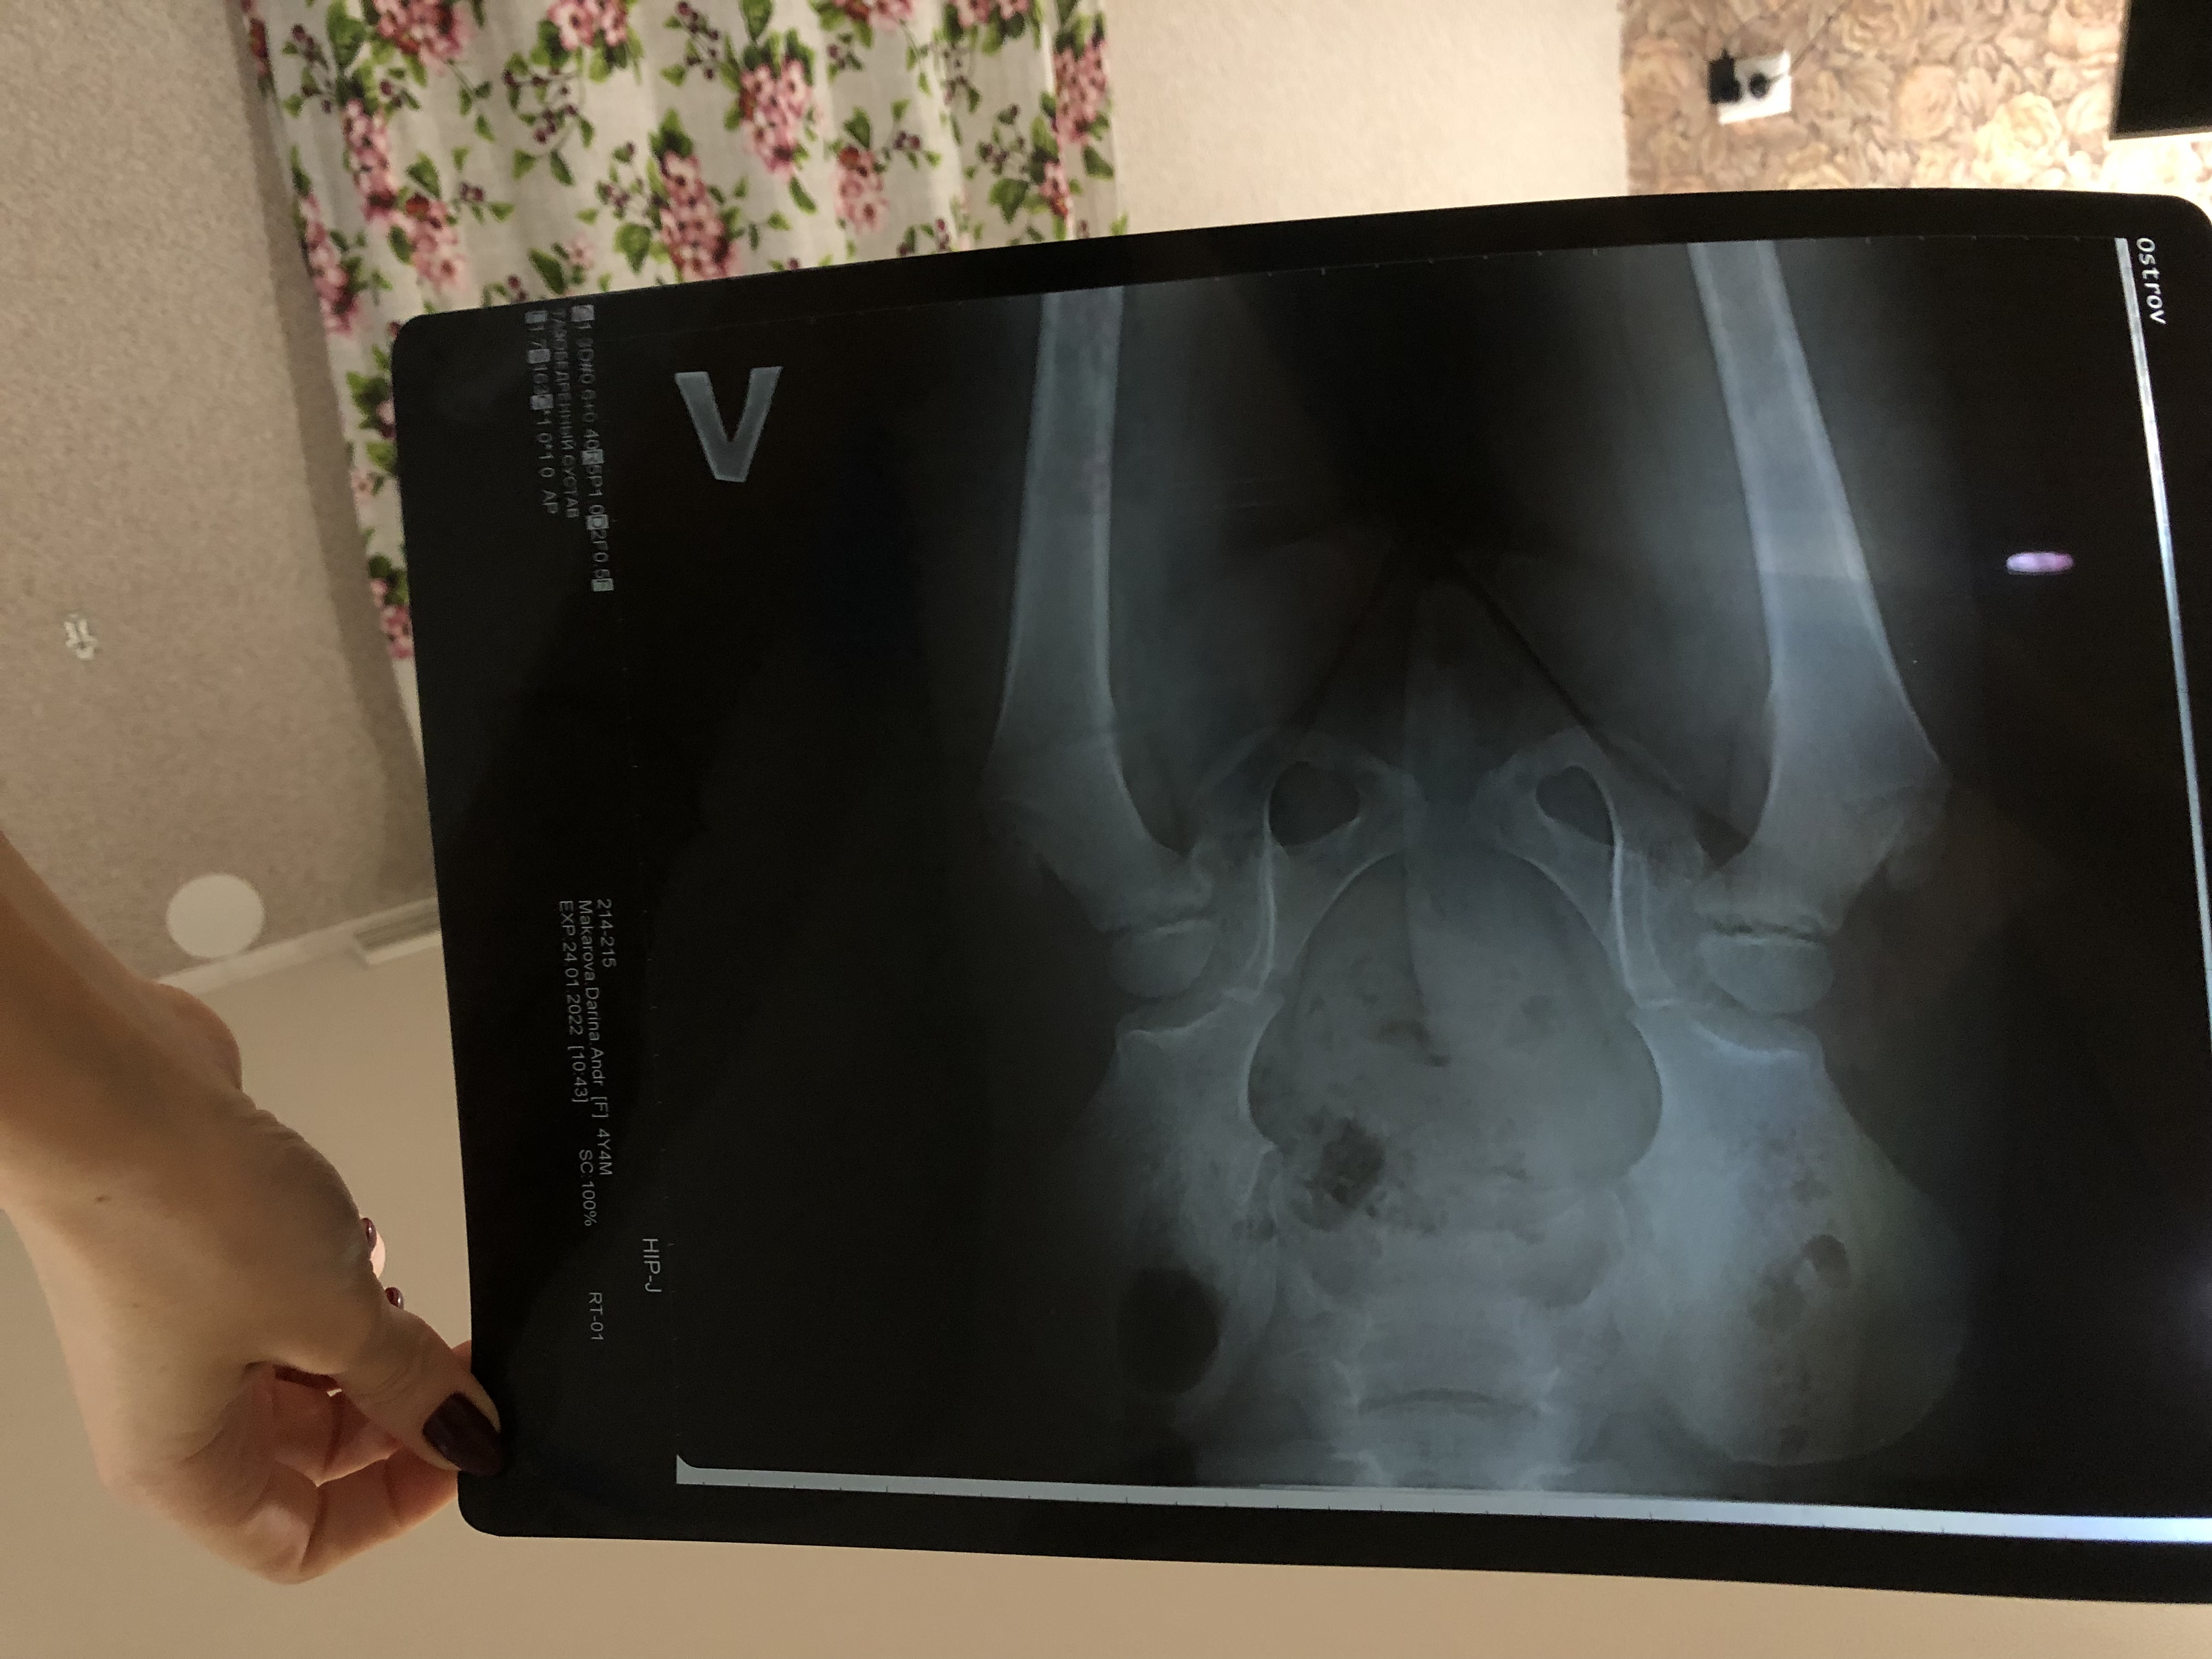

Врач

поставил болезнь Пертоса. Хотелось бы в это не верить и не знаю что дальше делать. Девочка 4 года. Про помощи в подтверждении или опровержении диагноза